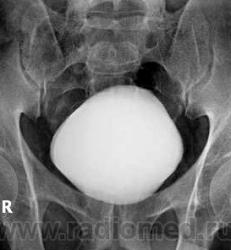

Иногда, незначительные боли в пояснице, анализы, как крови, так и мочи в норме. Временами, ночью, во сне мочеиспускание.

вторичный гидронефроз справа за счет частичной перегородки мочеточника на уровне L3. Большего мне из имеющихся исследований не выжать.